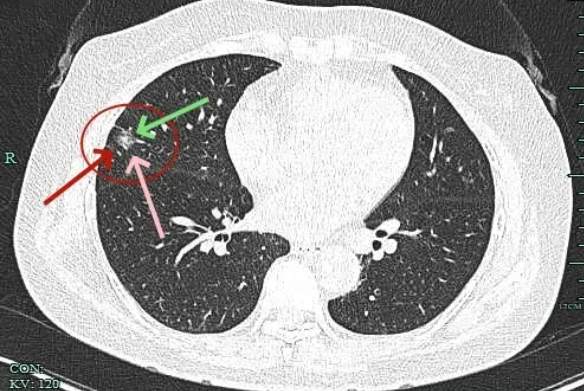

边缘不平有毛刺,实性成分开始出现,外周仍是磨玻璃密度的。血管与之关系密切。